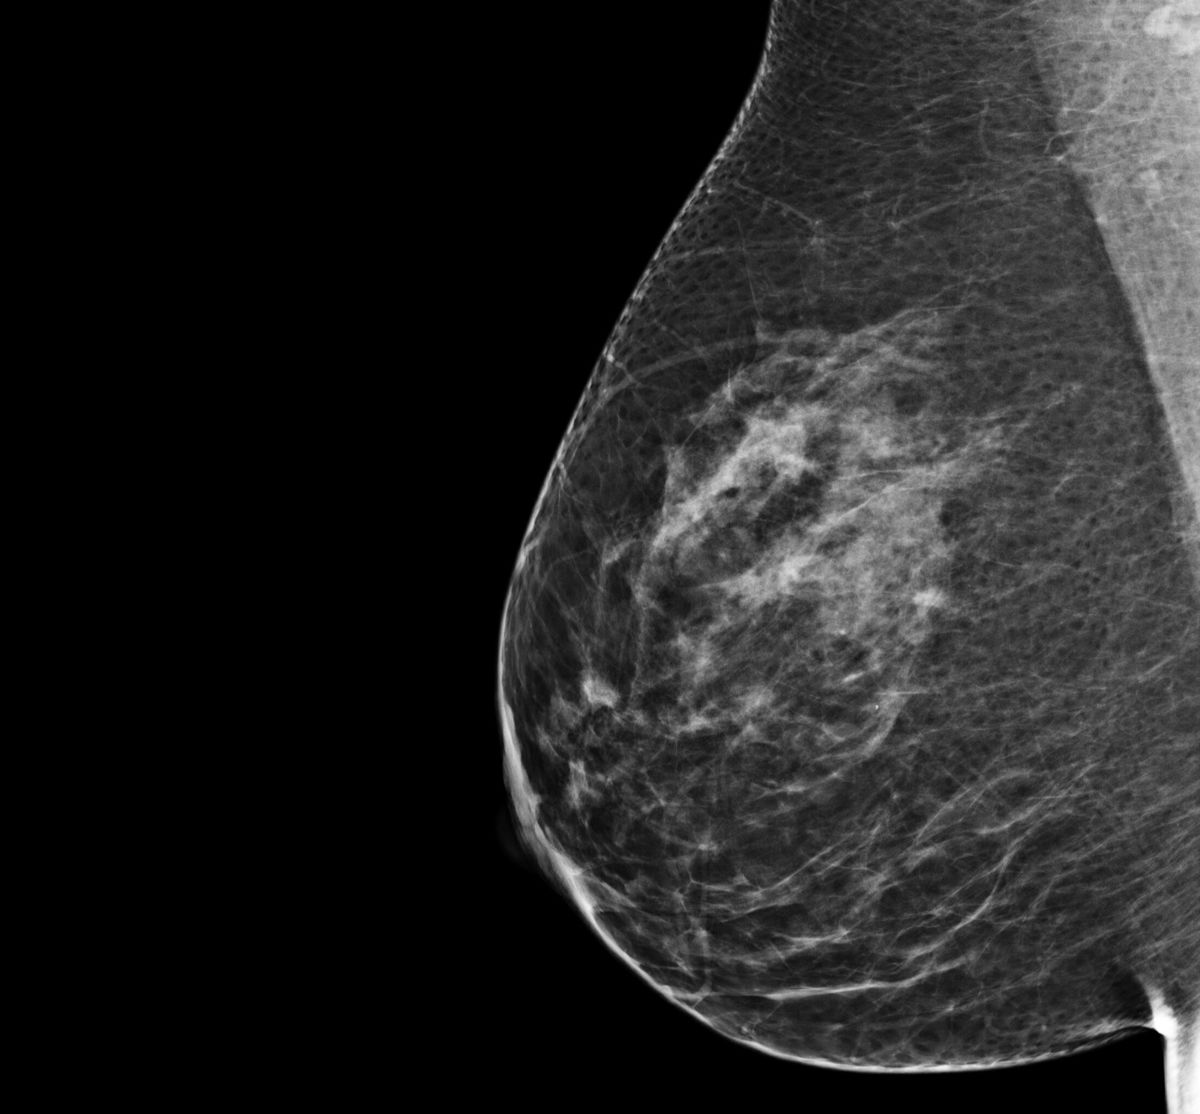

An example of a normal breast screen

Each screen may look a little different because all breasts are a little different.